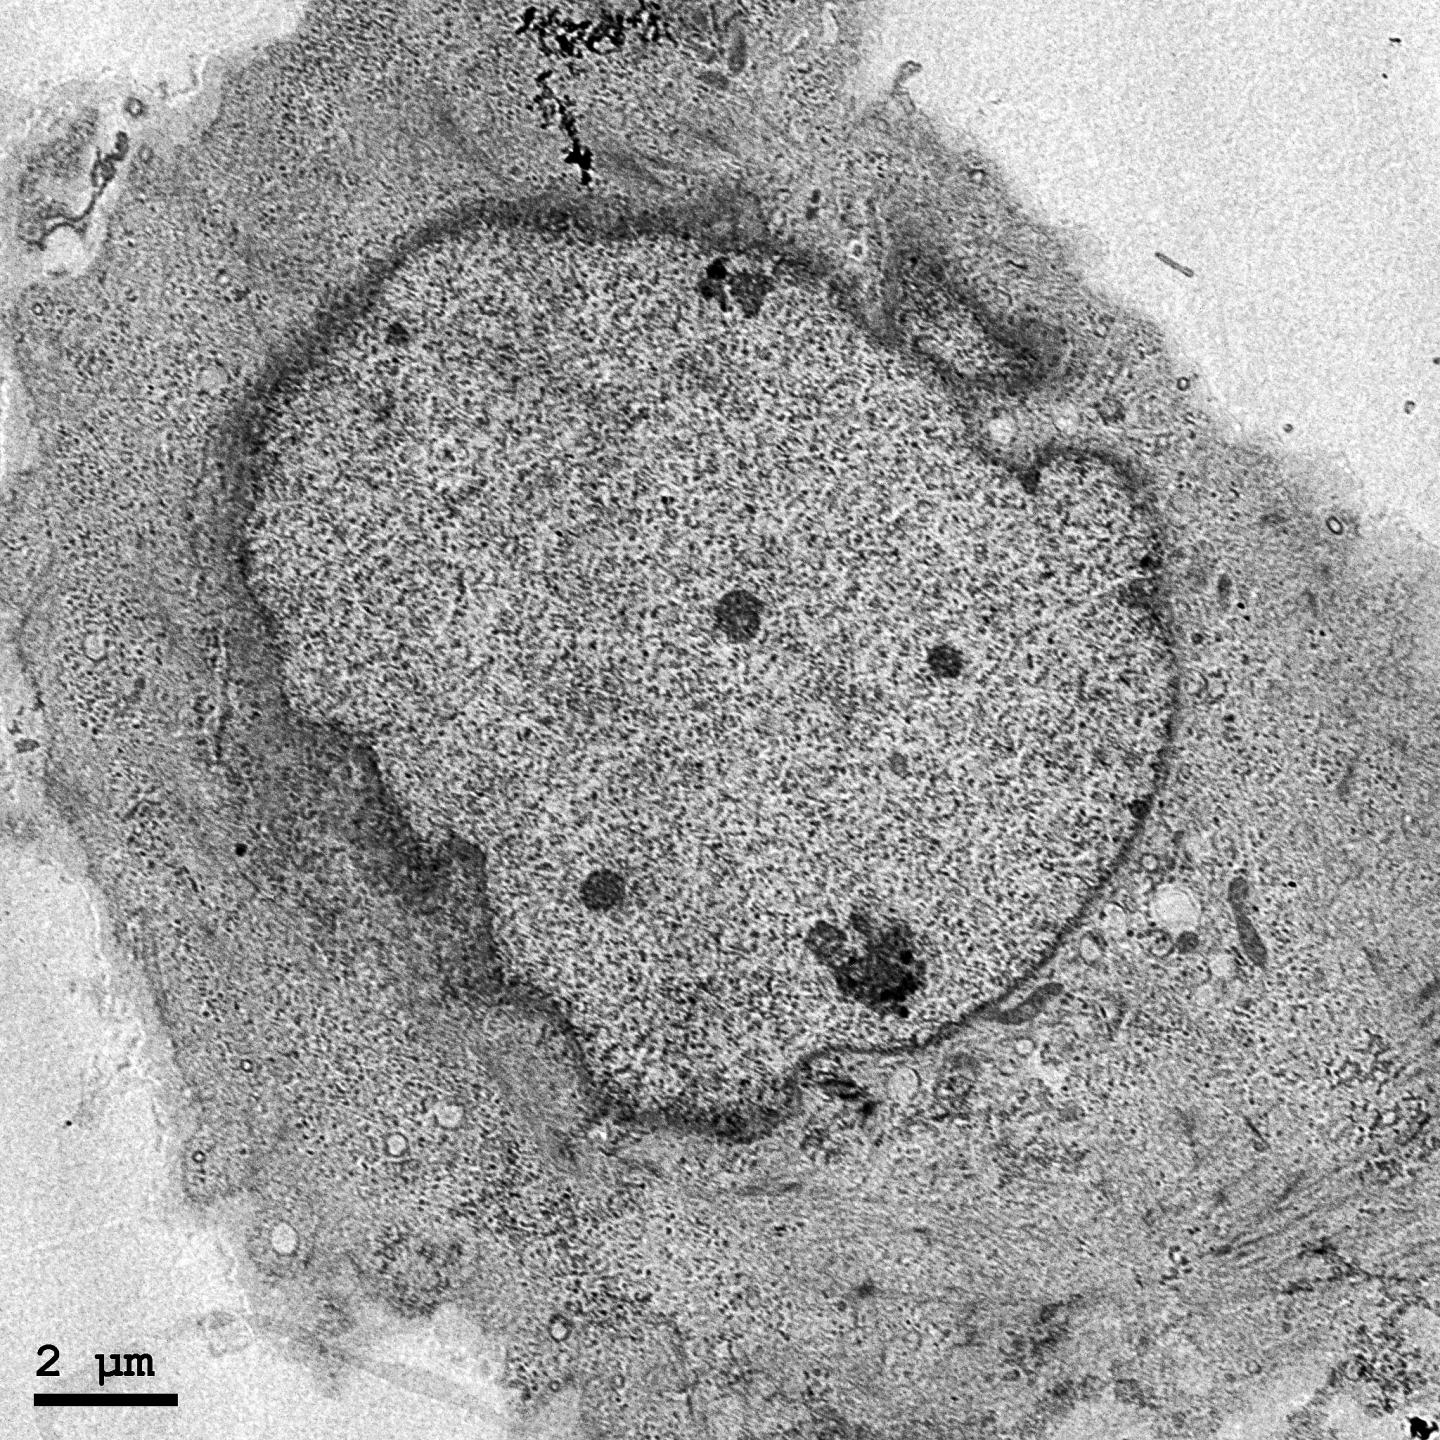

Recent research has shown that the cells in our bodies teeter on the brink of death. They possess intricate molecular mechanisms that promote either suicide or survival. The concept is known as programmed cell death (PCD). Since the early 2000s, when PCD was confirmed, research has focused mainly on finding genes and proteins that trigger it. however, processes aiding cell survival have not been well understood.

A recent paper published in Scientific Reports by researchers from Okinawa Institute of Science and Technology graduate University (OIST), establishes that in mouse cells, proteins comprising the CCR4-NOT complex are actively involved in regulation of a form of PCD called necroptosis. "It is one step toward deciphering the mechanisms of cell death," says Dr Toru Suzuki, group leader at the Cell Signal Unit, led by Prof. Tadashi Yamamoto.

About 10 years ago another form of PCD was discovered. It was named necroptosis, as it shares some characteristics of apoptosis, such as rigorous gene-level regulation, and necrosis, an inflammatory cell death in which the cell membrane swells and later breaks, leaking its contents into the intercellular space. Necroptosis can be a fail-safe mechanism in case apoptosis is inhibited, for example, by bacteria or viruses.

One of the key elements in CCR4-NOT's regulatory activity is one of its component proteins, CNOT3. Experiments conducted by Dr Suzuki's group showed that suppression of CNOT3 in mouse cells leads to necroptosis. In the CNOT3-depleted cells the stability and expression of mRNAs encoding RIPK1 and RIPK3 proteins, which are directly associated with necroptosis, are increased. This leads to build-up of death-triggering proteins and cell demise. These results suggest that some human inflammatory diseases associated with necrotic cell death, such as rheumatoid arthritis and psoriasis, may be caused by deregulation of the CCR4-NOT complex.